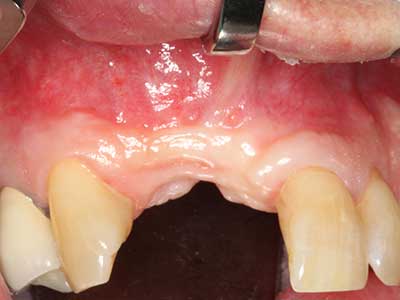

Фиг. 12: След шест месеца на заздравяване, алвеоларният гребен е добре оразмерен триизмерно.

Фиг. 13: Подходяща иригация с остатъчна 4 mm дебелина на костта е важна за този 52-годишен пациент по време на разделянето на костта.

Фиг. 16: Интраоралните условия също са стабилни с поставените импланти в кератизираната гингива.